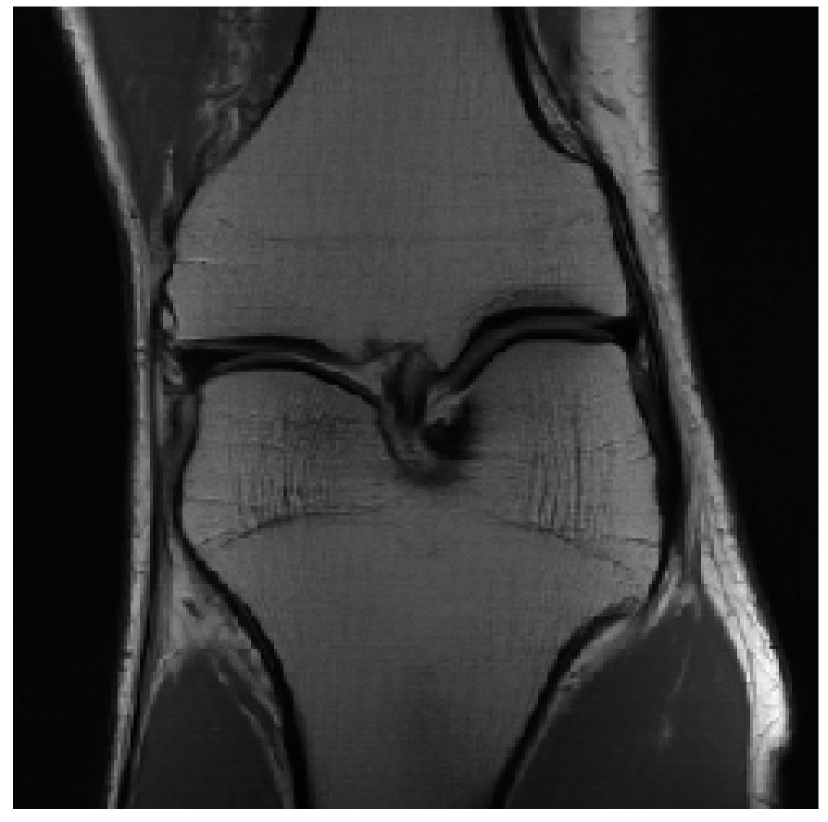

We evaluated our models on three data sets: the validation set as in Zbontar et al. (2018), and the test and challenge sets through the fastMRI website. A summary of these evaluations can be found in table 1111Results on the challenge data set will be added once publicly available.. To assess image quality more closely, we show some exemplary reconstructions from each model in figure 1.

Reconstruction

Reconstruction

Ground Truth

Reconstruction

Reconstruction